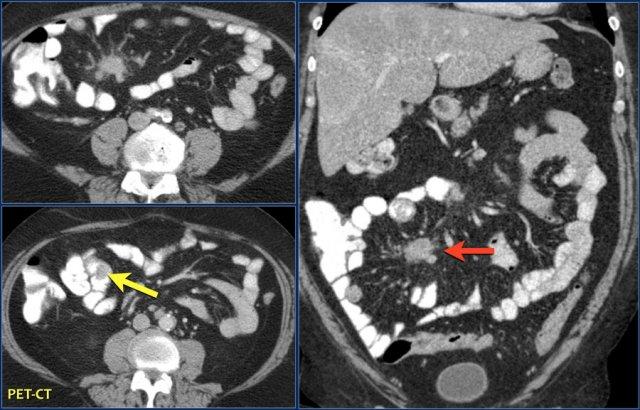

Các hình ảnh cho thấy một khối hình vòng ngắn gây tắc nghẽn ở hỗng tràng (mũi tên vàng) kèm hạch bạch huyết to (mũi tên đỏ).

Kết quả giải phẫu bệnh xác nhận là ung thư biểu mô tuyến.

Các hình ảnh phía trên cho thấy một khối hình vòng ở đoạn gần hỗng tràng có tăng hấp thu FDG (mũi tên vàng).

Các hình ảnh MRI phía dưới cho thấy cùng khối hỗng tràng đó với bờ dạng vai và hạch to mạc treo (mũi tên đỏ), phù hợp với ung thư biểu mô tuyến.